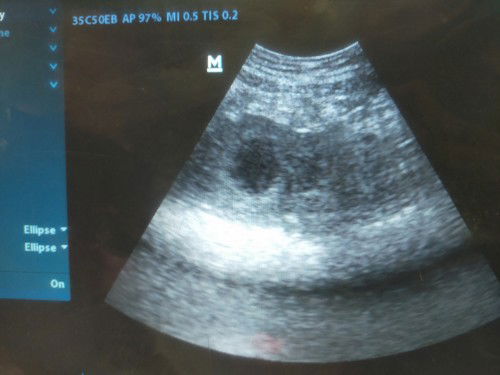

#seriusnanya saya waktu kontrol minggu kemarin pas usia kandungan baru masuk 7minggu, dan di usg melalui perut baru kelihatan kantong janinnya. Apakah itu normal bun?